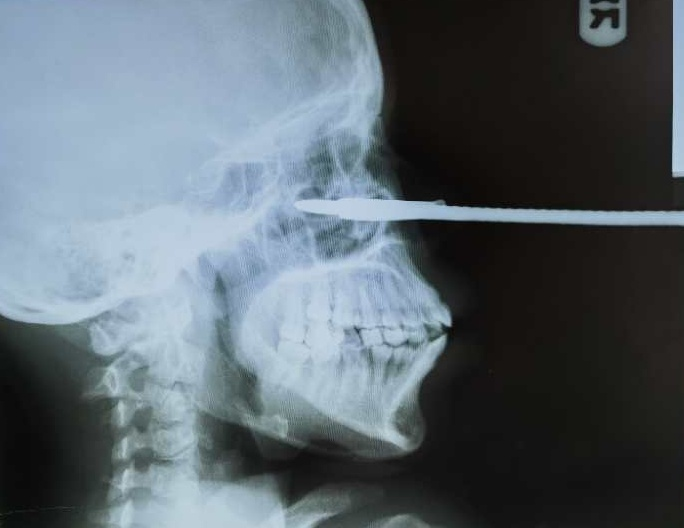

经过阅读患者的X线片,我发现鱼叉带有倒刺,非常锋利,倒刺已全部刺入组织内部,尖端已接近颅底。我立即联系CT室进行CT扫描,确定鱼叉经过的确切组织结构。不巧的是,CT机正在进行检修,无法使用。我再次对患者进行了详细的专科检查,并在阅片后仔细估算出鱼叉尖部应该到达右侧鼻咽部,颅底的骨质应该没有破坏。

Dr. Qian Jian did not eat lunch, rushing to the clinic department . He was surprised by the patient who was in extreme pain, keeping moaning, holding about 1m long metal harpoon in her hands, looking at everyone who approached her in horror.  Doctor Qian first comforted patient and then gived her trust. He assured her that he will try his best to help her solve the problem. After a while, patients mood gradually smoothed down, at this point,  Doctor Qian carefully chected the patient, surprised to find that metal harpoon about 1m long, close to 1cm in diameter, since the left alar, through the nasal space, into the right nasal cavity, has reached the right nasopharynx.  After reading the patient's X-ray, Dr. Qian found that the harpoon had a sharp barb that had all penetrated into the tissue, close to the base of the skull . Qian Jian immediately contacted the CT room performing a CT scan to determine the exact tissue structure that the harpoon passed through. Unfortunately, the CT machine was undergoing maintenance and cannot be used. Dr. Qian again conducted a detailed specialist examination of the patient, and after reading the film, carefully estimated that the tip of the harpoon should reach the right nasopharynx, and the bone of the skull base should not be destroyed.